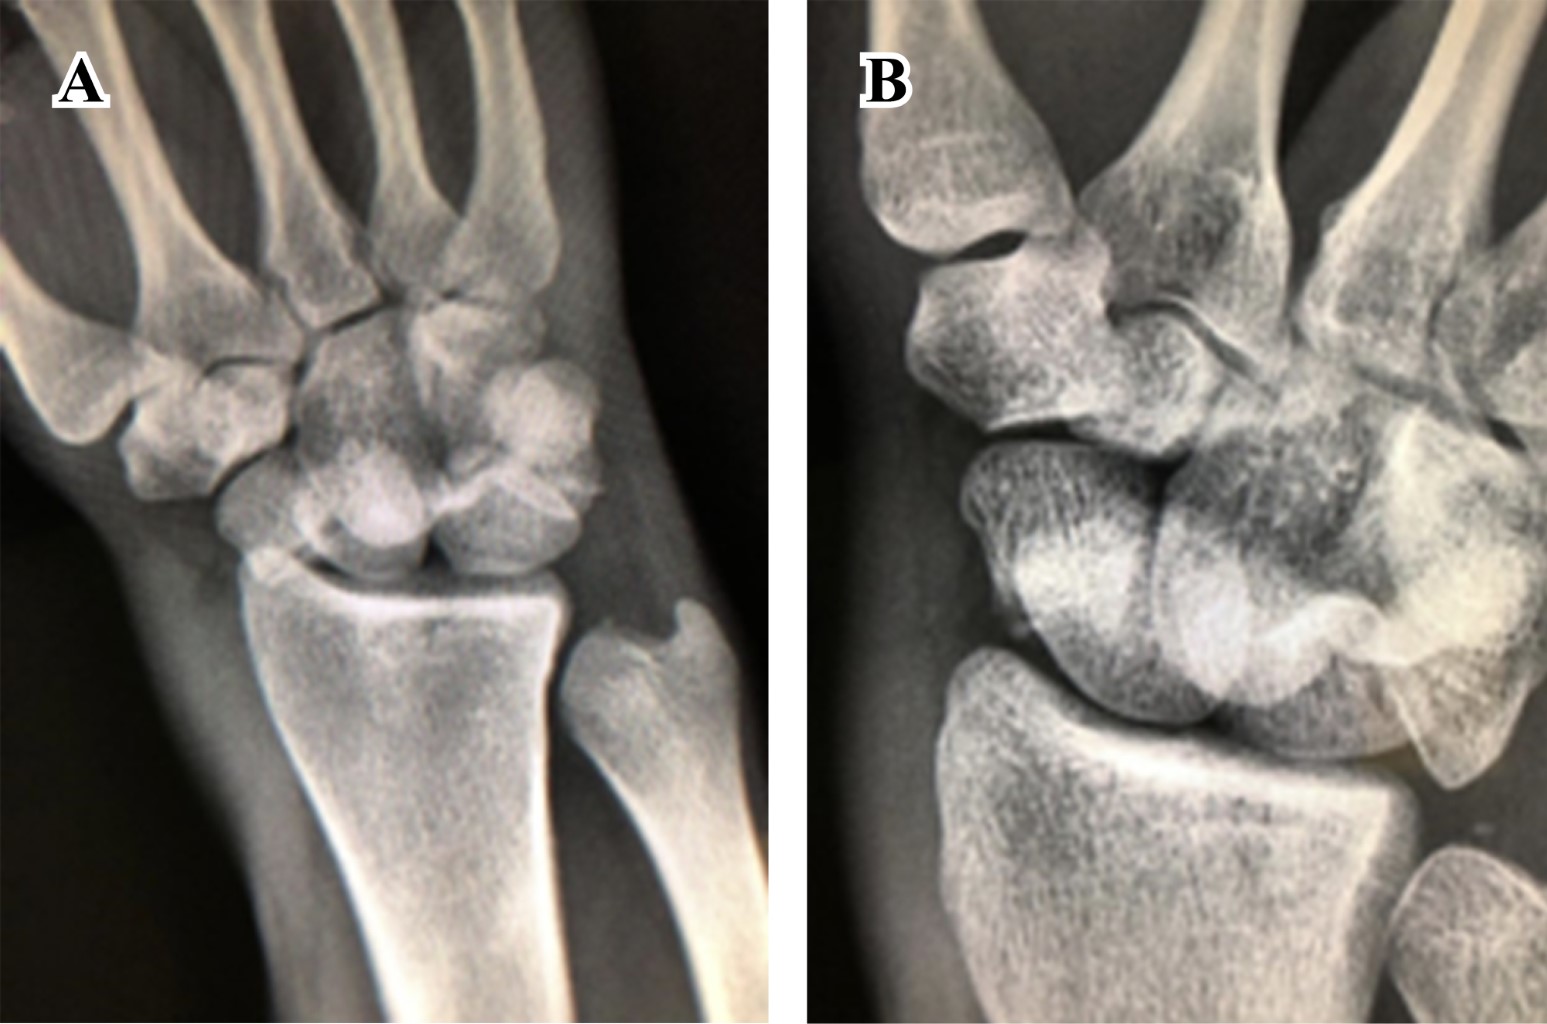

Tres días después del traumatismo, bajo anestesia general, se realiza abordaje dorsal para escafoides. Luego, bajo control fluoroscópico, se coloca clavillo Kirschner como guía. Después de corroborada adecuada colocación, se completa osteosíntesis con tornillo tipo Herbert de 2.5 mm.

Posteriormente se reconstruye ligamento escafosemilunar con ancla metálica Micro Corkscrew (Arthrex®) de 2.2 mm. Después se colocan dos clavillos Kirchner de 1.2 mm, el primero transescafo-perilunar y el segundo fijando piramidal y semilunar (Figura 4). Se realizan maniobras dinámicas posterior a la osteosíntesis, demostrando adecuada estabilidad en huesos del carpo. Se realiza cierre por planos y es inmovilizado nuevamente con férula tipo pinza de azúcar; solamente fue removido a las dos semanas para el retiro de puntos. A las seis semanas, se retiran clavillos Kirschner y se inicia fisioterapia. Se realizó seguimiento esporádico: regreso a actividades de la vida diaria a los tres meses del procedimiento, con rangos de movilidad completos y sin dolor. A 18 meses después del traumatismo, el paciente se encuentra asintomático y sin complicaciones radiológicas (Figura 5).

Figura 4

Figura 5